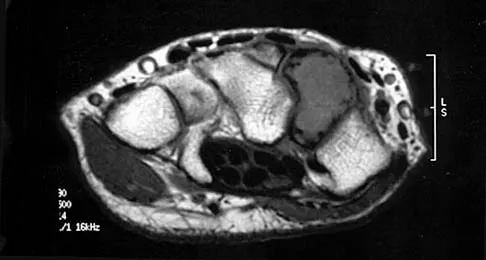

Figures 5a and 5b show axial and coronal MRI images of the left ankle of a patient with lateral ankle pain. What is the most likely diagnosis?

Explanation